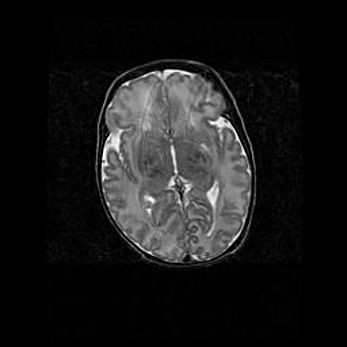

Церебральная ишемия II.

Возраст: 5 дней

Вес: 3400 г

Пол: женский

Окружность головы: 35 см

Срок гестации: 39 недель

Церебральная ишемия – это заболевание, характеризующееся недостаточностью (гипоксией) либо полным прекращением (аноксией) снабжения мозга кислородом по причине закупорки одного или нескольких сосудов. Это приводит к  что метаболическим расстройствам различной степени тяжести в тканях головного мозга, развитию коагуляционных некрозов и гибели нейронов.